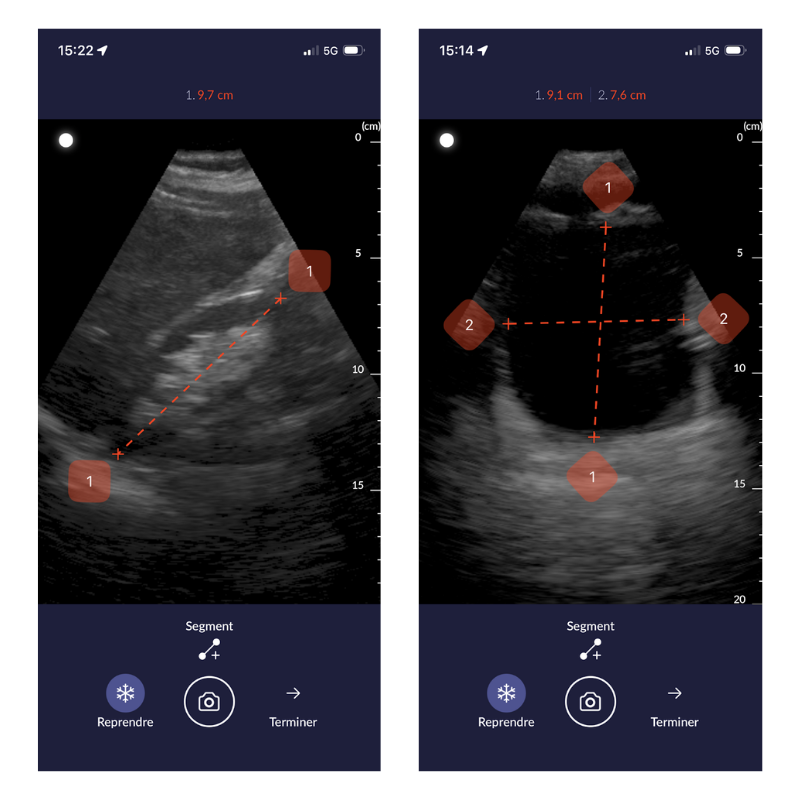

Un nouvel outil d’évaluation des distances

La version 2.40 introduit également un outil d’évaluation des distances, utilisable uniquement lorsque l’image est figée.

- Évaluer une distance entre deux points sur une image figée.

- Obtenir une appréciation plus objective de certaines distances.

- Enrichir les discussions en staff, les analyses pédagogiques et les relectures.